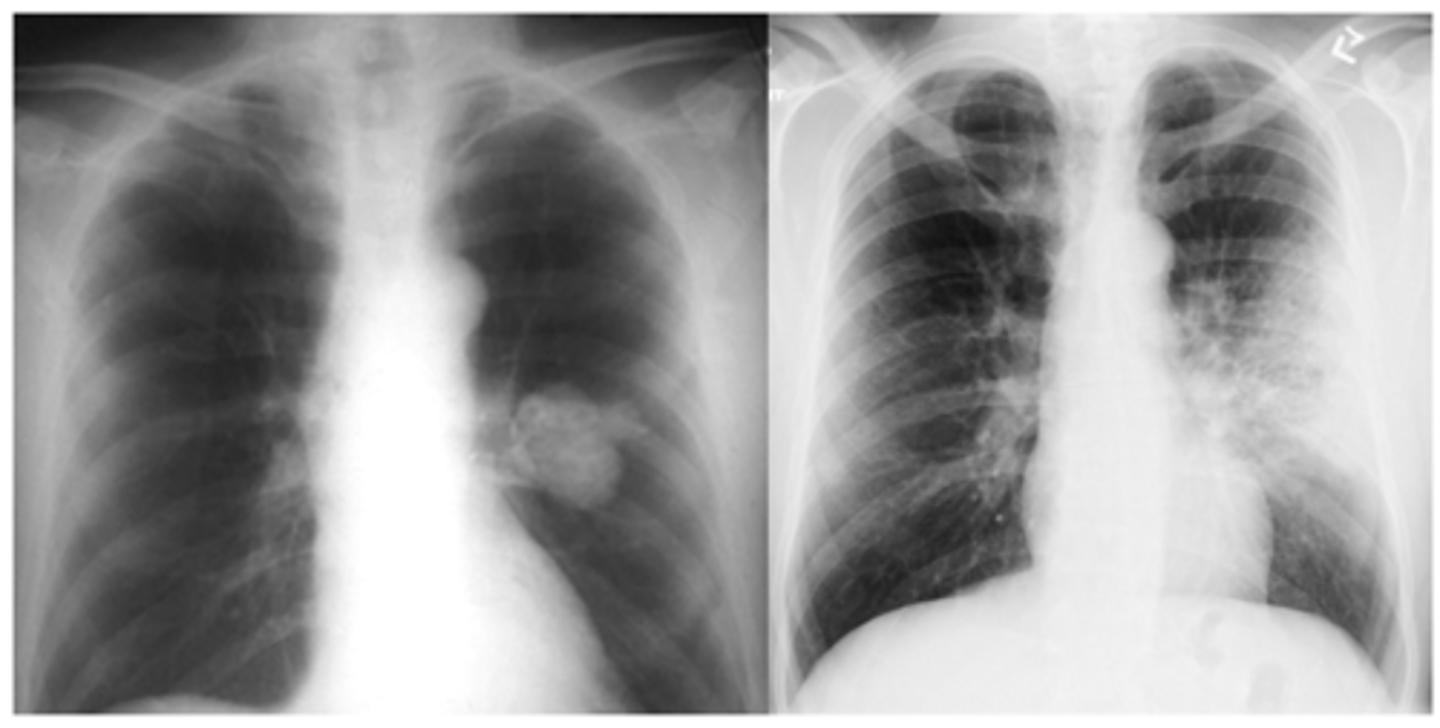

dx on back

left lower lobe pneumonia

<p>left lower lobe pneumonia</p>

ID mass and infiltrate on back

mass Left

infiltrate R

<p>mass Left</p><p>infiltrate R</p>